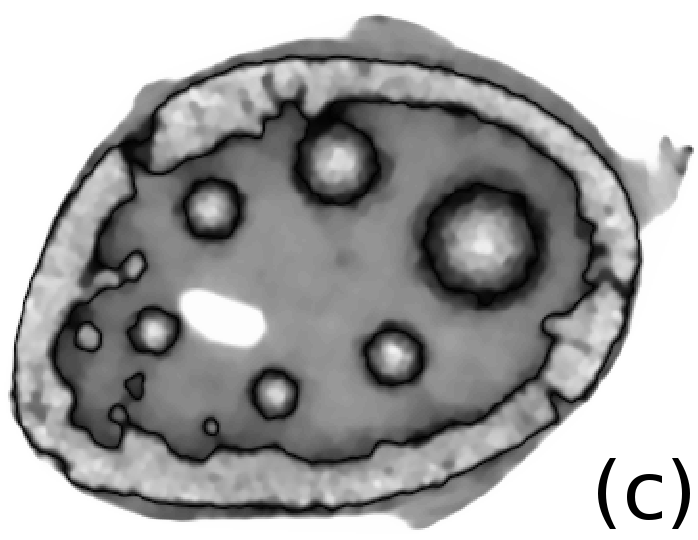

Reconstructed images are presented in Fig. 4. Since CGLS-TV- reconstruction might look more appealing than CGLS-EL we also show the surface representations of reconstructed images (see Fig. 5) and horizontal middle cross-sections (see Fig. 6).

One can notice that CGLS reconstruction is very noisy. CGLS-TV method better suppresses noise, however smooth features are strongly affected by the “staircasing” effect. CGLS-TV- method provides reconstruction with smoother features and CGLS-EL method resolves smooth features even better (e.g. cone-shaped parabola). Although CGLS-EL method performs very well for smooth objects one can notice the wave-like variations of intensity in the background and also at the top of the rectangle (see Fig. 6). This issue can be explained by the properties of our regularizer, in contrast to TV, our penalty does not seek the sparsest solution and does not penalize strongly (pushing to the constant value) a small intensity perturbations. The EL term tends to preserve all sharp edges while uniform noise is smoothed isotropically with the Laplacian. In Fig. 6 one can see that the CGLS-EL method provides better recovery of smooth features while slightly higher (compare to TV and TV-) perturbations visible in uniform areas (the top of the rectangle), however, the edges of the rectangle are defined sharper with the EL penalty.

In Fig. 10 and 11 one can notice that the BR is very smooth for TV and TV- penalties and some long-wave oscillations can be seen in the reconstructed image with EL penalty. This result corresponds to the expected behaviour of the EL penalty. We note here that the phantoms background (see Fig. 7) is not as flat as TV and TV- penalty recovered it. Furthermore, a small size dot-like feature (approximately in the centre of the phantom) is almost smoothed out with TV and TV- recovery. However, it is visible and well recovered with EL penalty. The sharp features, overall, are reconstructed very well with MLEM-EL method and seem even sharper compare to other methods (see the bone outer rim in Fig 10).